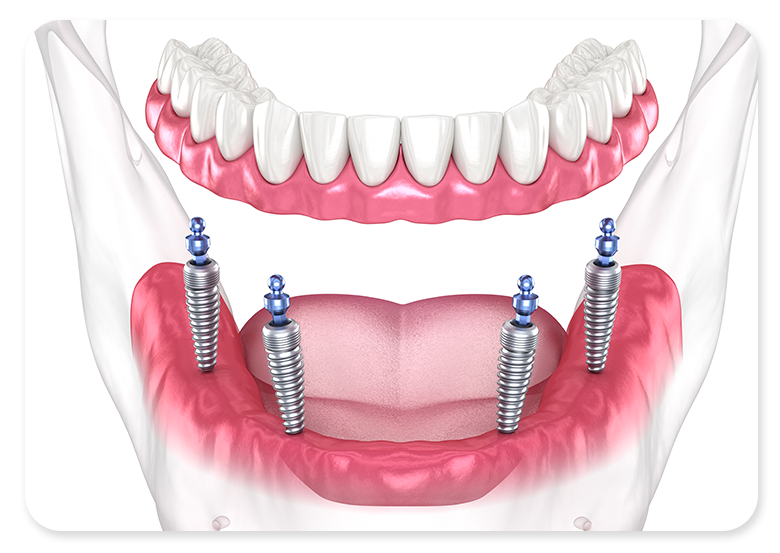

다양한 요인으로 인해 치아를 다수 상실하였거나

모두 상실하여 제 기능을 수행할 수 없는 경우

전반적인 범위에 임플란트를 수복하여

자연치아의 기능과 심미를 대체할 수 있는 치료법입니다.

구강 상태에 따라 6 - 10개 정도의 고정체를 식립한 후

연결된 형태의 인공치아를 제작하여 장착합니다.